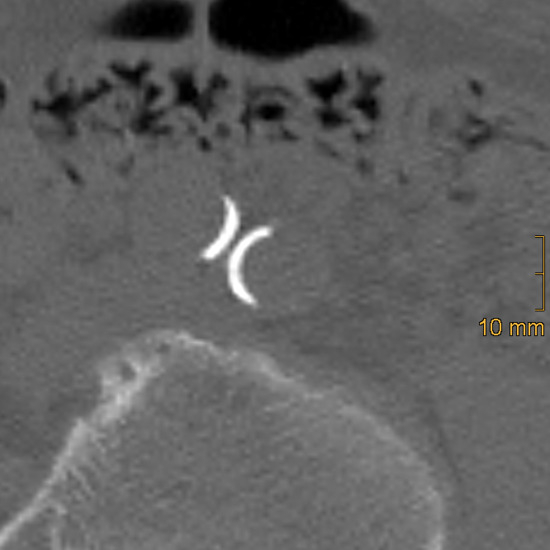

Gossypiboma, a Rare Cause of Abdominal Pain: A Case Report

Gossypiboma is a retained surgical item, most commonly gauze or sponge, inadvertently left inside a patient’s body after surgery. Although preventable, it can cause severe complications and is often underreported due to medicolegal concerns. We present a case of a 61-year-old woman who experienced left lower abdominal pain for three days. Her history included lumbar disc surgery via the lower left abdomen a decade earlier. Physical examination revealed a non-tender pelvic mass, and abdominal computed tomography (CT) showed a 4.5 × 4.7 × 6.1 cm high-attenuation lesion with internal low-attenuation areas in the left retroperitoneal space. The mass was surgically removed, and gauze material was identified inside, confirming the diagnosis of gossypiboma. The patient recovered uneventfully postoperatively. Gossypiboma can present with subacute or chronic symptoms, making diagnosis challenging. While uncommon, gossypiboma should be considered in differential diagnoses of patients with unexplained abdominal masses and prior surgical history. Prompt surgical management is essential to prevent complications. This case highlights the importance of meticulous surgical counts and awareness of this rare but serious condition. Full article